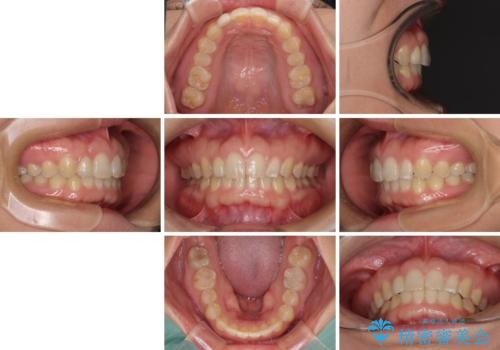

- 前歯の空隙と矮小歯を気にして来院された患者様です。

上下の歯列不正はインビザラインにより整えることとしました。

矯正治療の後に、前歯1歯と奥歯をオールセラミックにて治療することとしました。

矯正治療により矮小歯前後にスペースを作りながら歯列を整え、セラミッククラウン装着後に最終的に歯列と咬合を仕上げました。